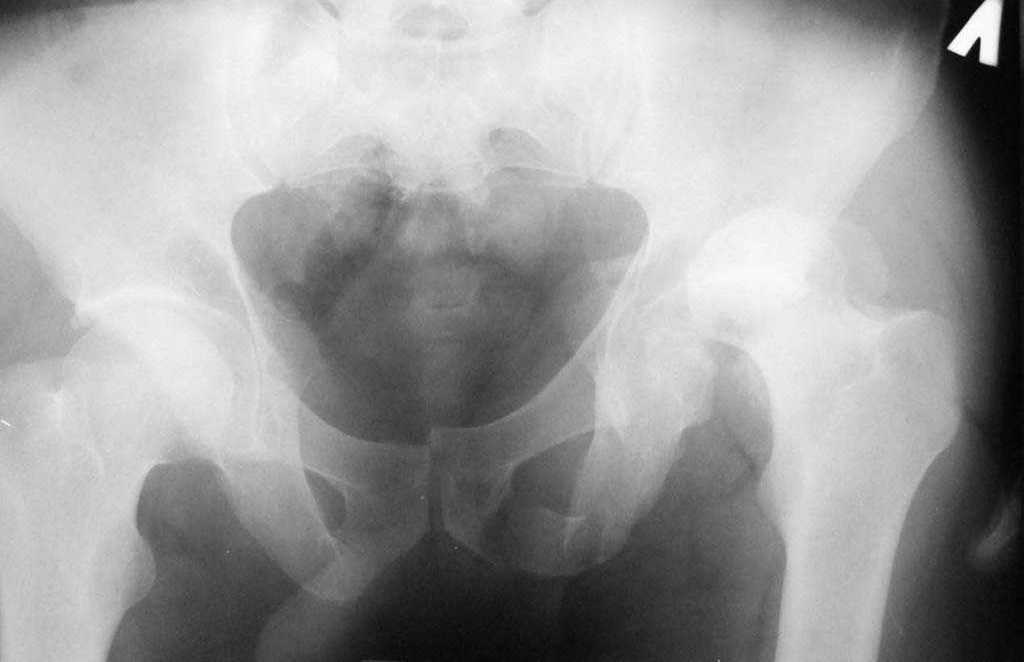

еще одно дополнение